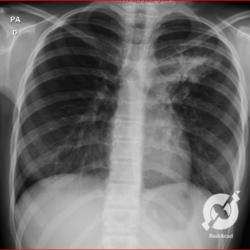

E o nome dado a esta alteração radiográfica que corresponde à substituição do ar alveolar por líquido é a consolidação alveolar.

Uma consolidação alveolar é, por definição, uma opacidade (imagem densa, branquinha) homogênea ou às vezes heterogênea (pela presença de calcificações ou cavidades), de limites mal definidos, exceto quando toca a pleura da parede ou das cissuras pulmonares. É um termo usado tanto em radiografia, como em tomografia computadorizada. Na tomografia, um outro termo é usado: vidro fosco, que é uma opacidade (branquinha mas não tanto como a consolidação), que borra o pulmão mas deixa ver os vasos de permeio (igual bigode de adolescente: dá pra ver todo o fundo).

Nós vamos mostrar aqui um pequeno apanhado de pneumonias de variados agentes, em diversos segmentos e lobos pulmonares, com extensões variadas. O objetivo é identificar o padrão radiológico de consolidação alveolar e não determinar o agente infeccioso, isso vai ser assunto para mais adiante. Aliás já antecipo que é fundamental saber localizar a lesão, porque alguns destes bichos gostam de determinados segmentos, alguns tumores também têm as suas preferências, então localização é fundamental. Se localização não fosse importante, um apartamento na beira do mar sairia o mesmo preço de um apartamento de frente pra BR-101, concordam?

Seguem alguns dos nossos casos de pneumonia para vocês treinarem os olhos e não se apavorarem nos plantões.